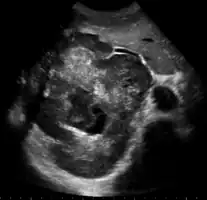

| Left lobe liver tumor in 50-year-old man | |